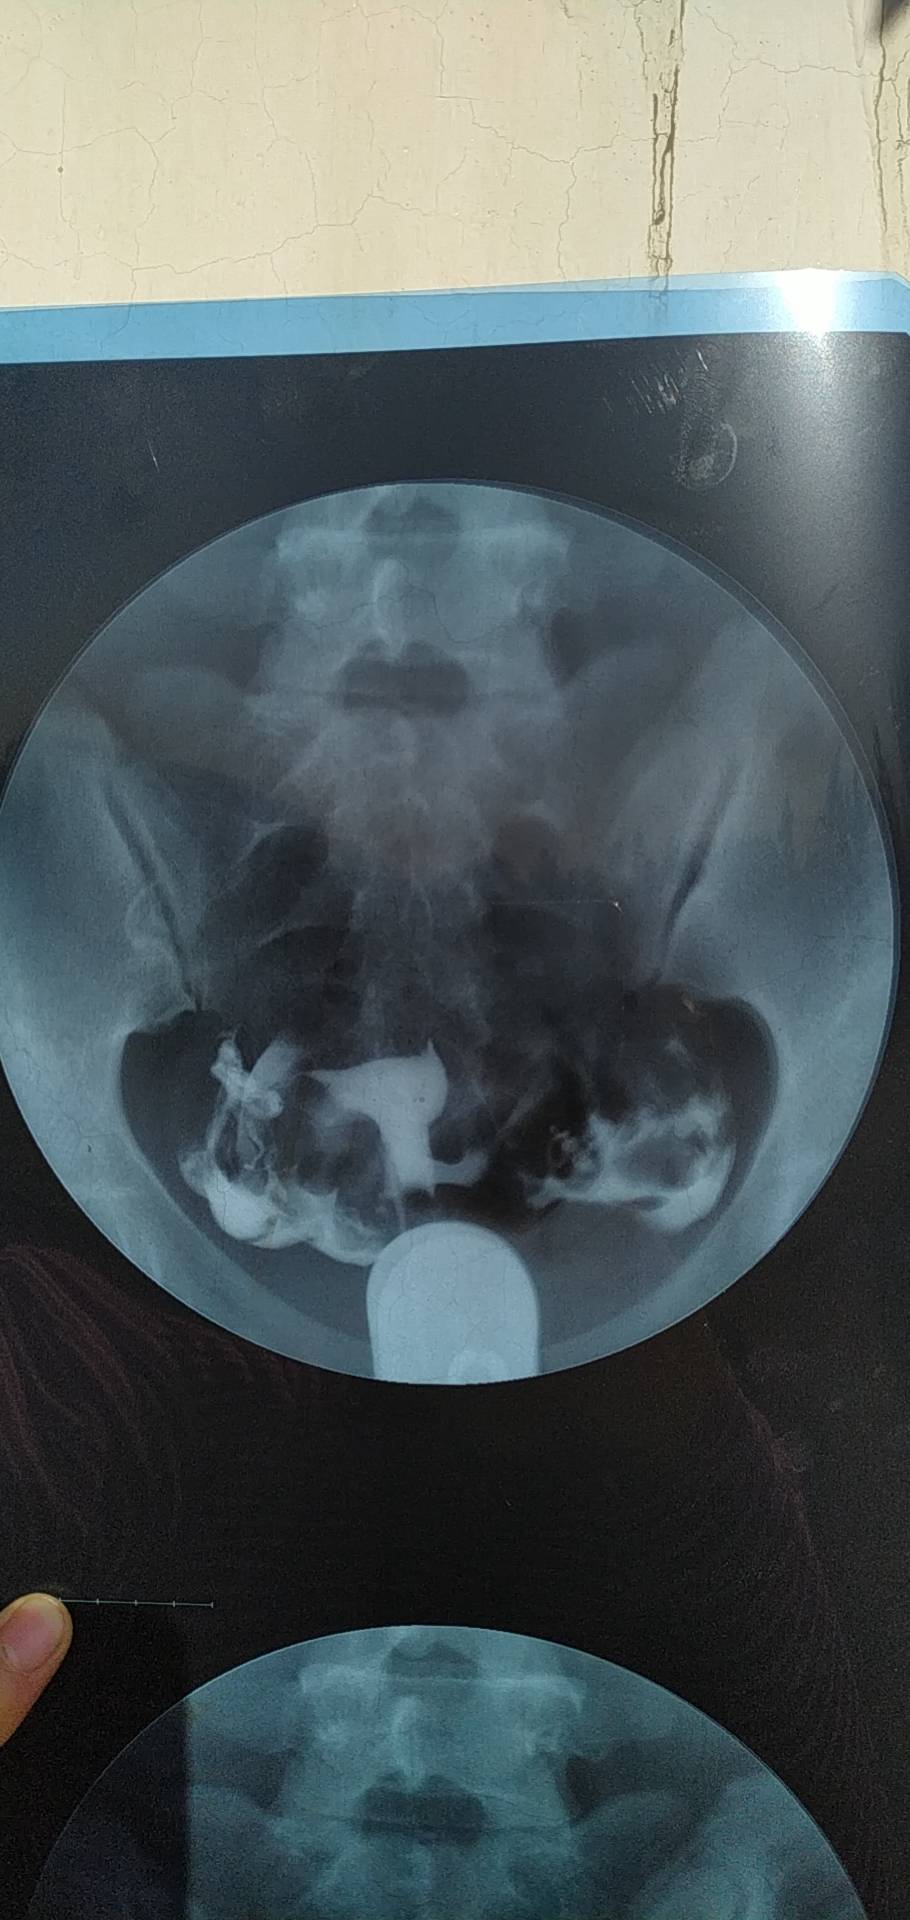

今年七月份做的造影显示输卵管通而不畅伴随多囊